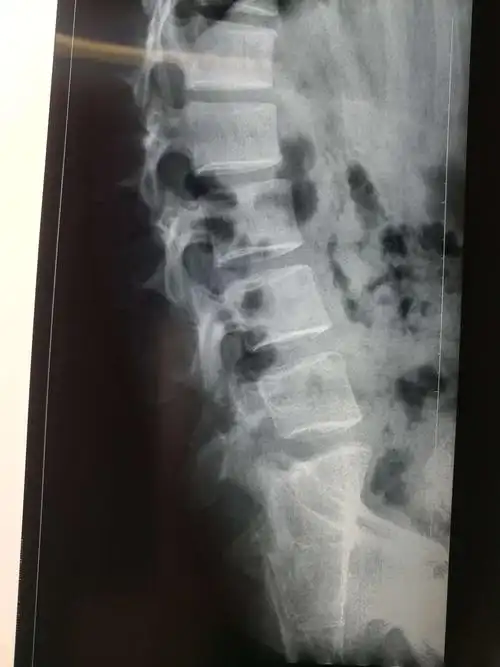

儿童个案:认识隐性脊椎裂

今天又有一例s1隐裂

什么是腰椎峡部裂

腰椎峡部裂,滑脱 - 好大夫在线

腰椎峡部裂1例

腰椎隐裂

病例:峡部裂导致腰椎滑脱该怎么治疗?